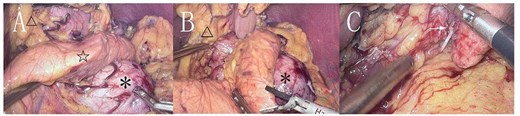

During surgery, a lump was identified behind the tail of the pancreatic body, with no apparent adhesion or invasion of the surrounding area. The pancreatic tail was completely freed and suspended along with the splenic artery and vein, revealing that the mass originated from the lesser curvature of the stomach (Fig. 2). After fully dissociating the mass, the gastric tissue was separated from it along the lesser curvature, and the mass was completely removed from the surface of the left renal vein. The mass, visible to the naked eye, measured approximately 5 × 6 cm (Fig. 3), and yellow viscous content was observed upon incision. Postoperative pathological examination revealed a retroperitoneal mass. The fibrous cyst wall tissue was lined with ciliated columnar epithelium, with numerous foam cells and lymphocyte infiltration, suggesting a diagnosis of bronchogenic cyst (Fig. 3). The postoperative diagnosis included gastric bronchogenic cyst, gallbladder stones with chronic cholecystitis, and coronary atherosclerotic heart disease. The patient received postoperative symptomatic treatment, including antiinfection therapy and fluid replacement. A follow-up abdominal CT scan six days after surgery showed no obvious residual cysts (Fig. 1C), and the patient was discharged.

A: The cyst seen with the naked eye, displaying a clear boundary. B: HE staining under a light microscope (10 × 20 magnification) showing the cyst wall tissue, with ciliated columnar epithelium, foam cells, and lymphocytes visible.